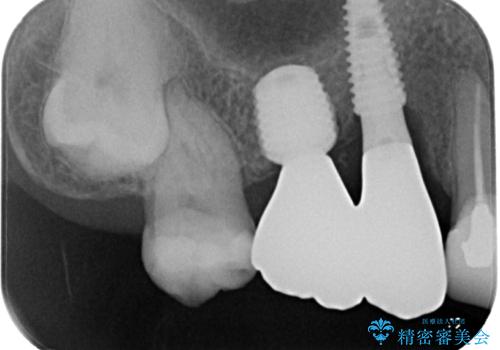

本来であれば、下顎の歯列を整えることで、上下がタイトに咬み合わせるように仕上げるべきでしたが、予算の都合で上顎のインプラント補綴治療のみを行うこととなりました。